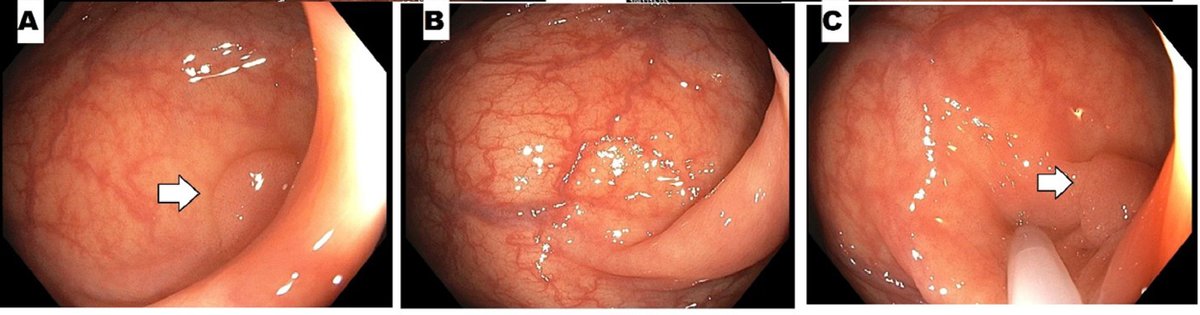

๐Ÿ”Ž ACG Case Reports Journal ๐Ÿ” Large Chicken Bone Impacted in Colonic Diverticulum Mimicking Diverticulitis Stoskute, et al. ๐Ÿ‘‰ bit.ly/3ixAJ2B Asim Shuja, MD #GIfellows #GItwitter

๐Ÿ”Ž ACG Case Reports Journal ๐Ÿ”

Large Chicken Bone Impacted in Colonic Diverticulum Mimicking Diverticulitis

Stoskute, et al.

๐Ÿ‘‰ bit.ly/3ixAJ2B

<a href="/AsimShuja11/">Asim Shuja, MD</a> #GIfellows #GItwitter